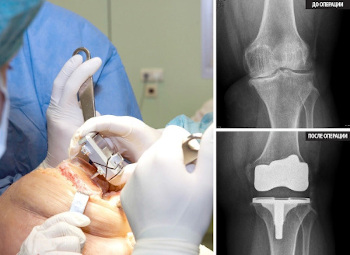

Zamjena zgloba je veoma skupa i veoma ozbiljna operacija.

Endoproteza koljenskog zgloba, fotografija.